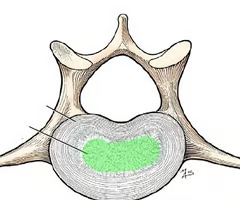

Intervertebral disc (cushion-like pad made of 2 parts)

Nucleus pulposus

Inner gelatinous material that acts like a rubber ball to give disc elasticity and compressibility

Annulus fibrosus

Strong collar surrounding nucleus pulposus; made of fibrocartilage and collagen fibus.

Nucleus pulposus

Annulus fibrosus